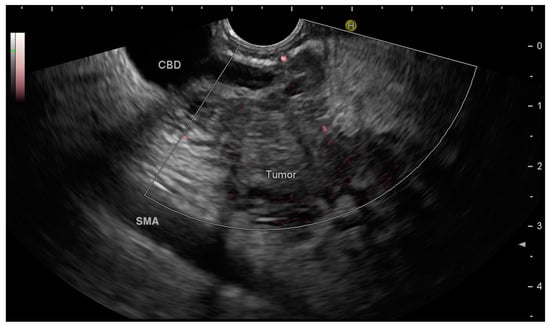

3.3.1. Site and Characteristics of the Pancreatic Lesion